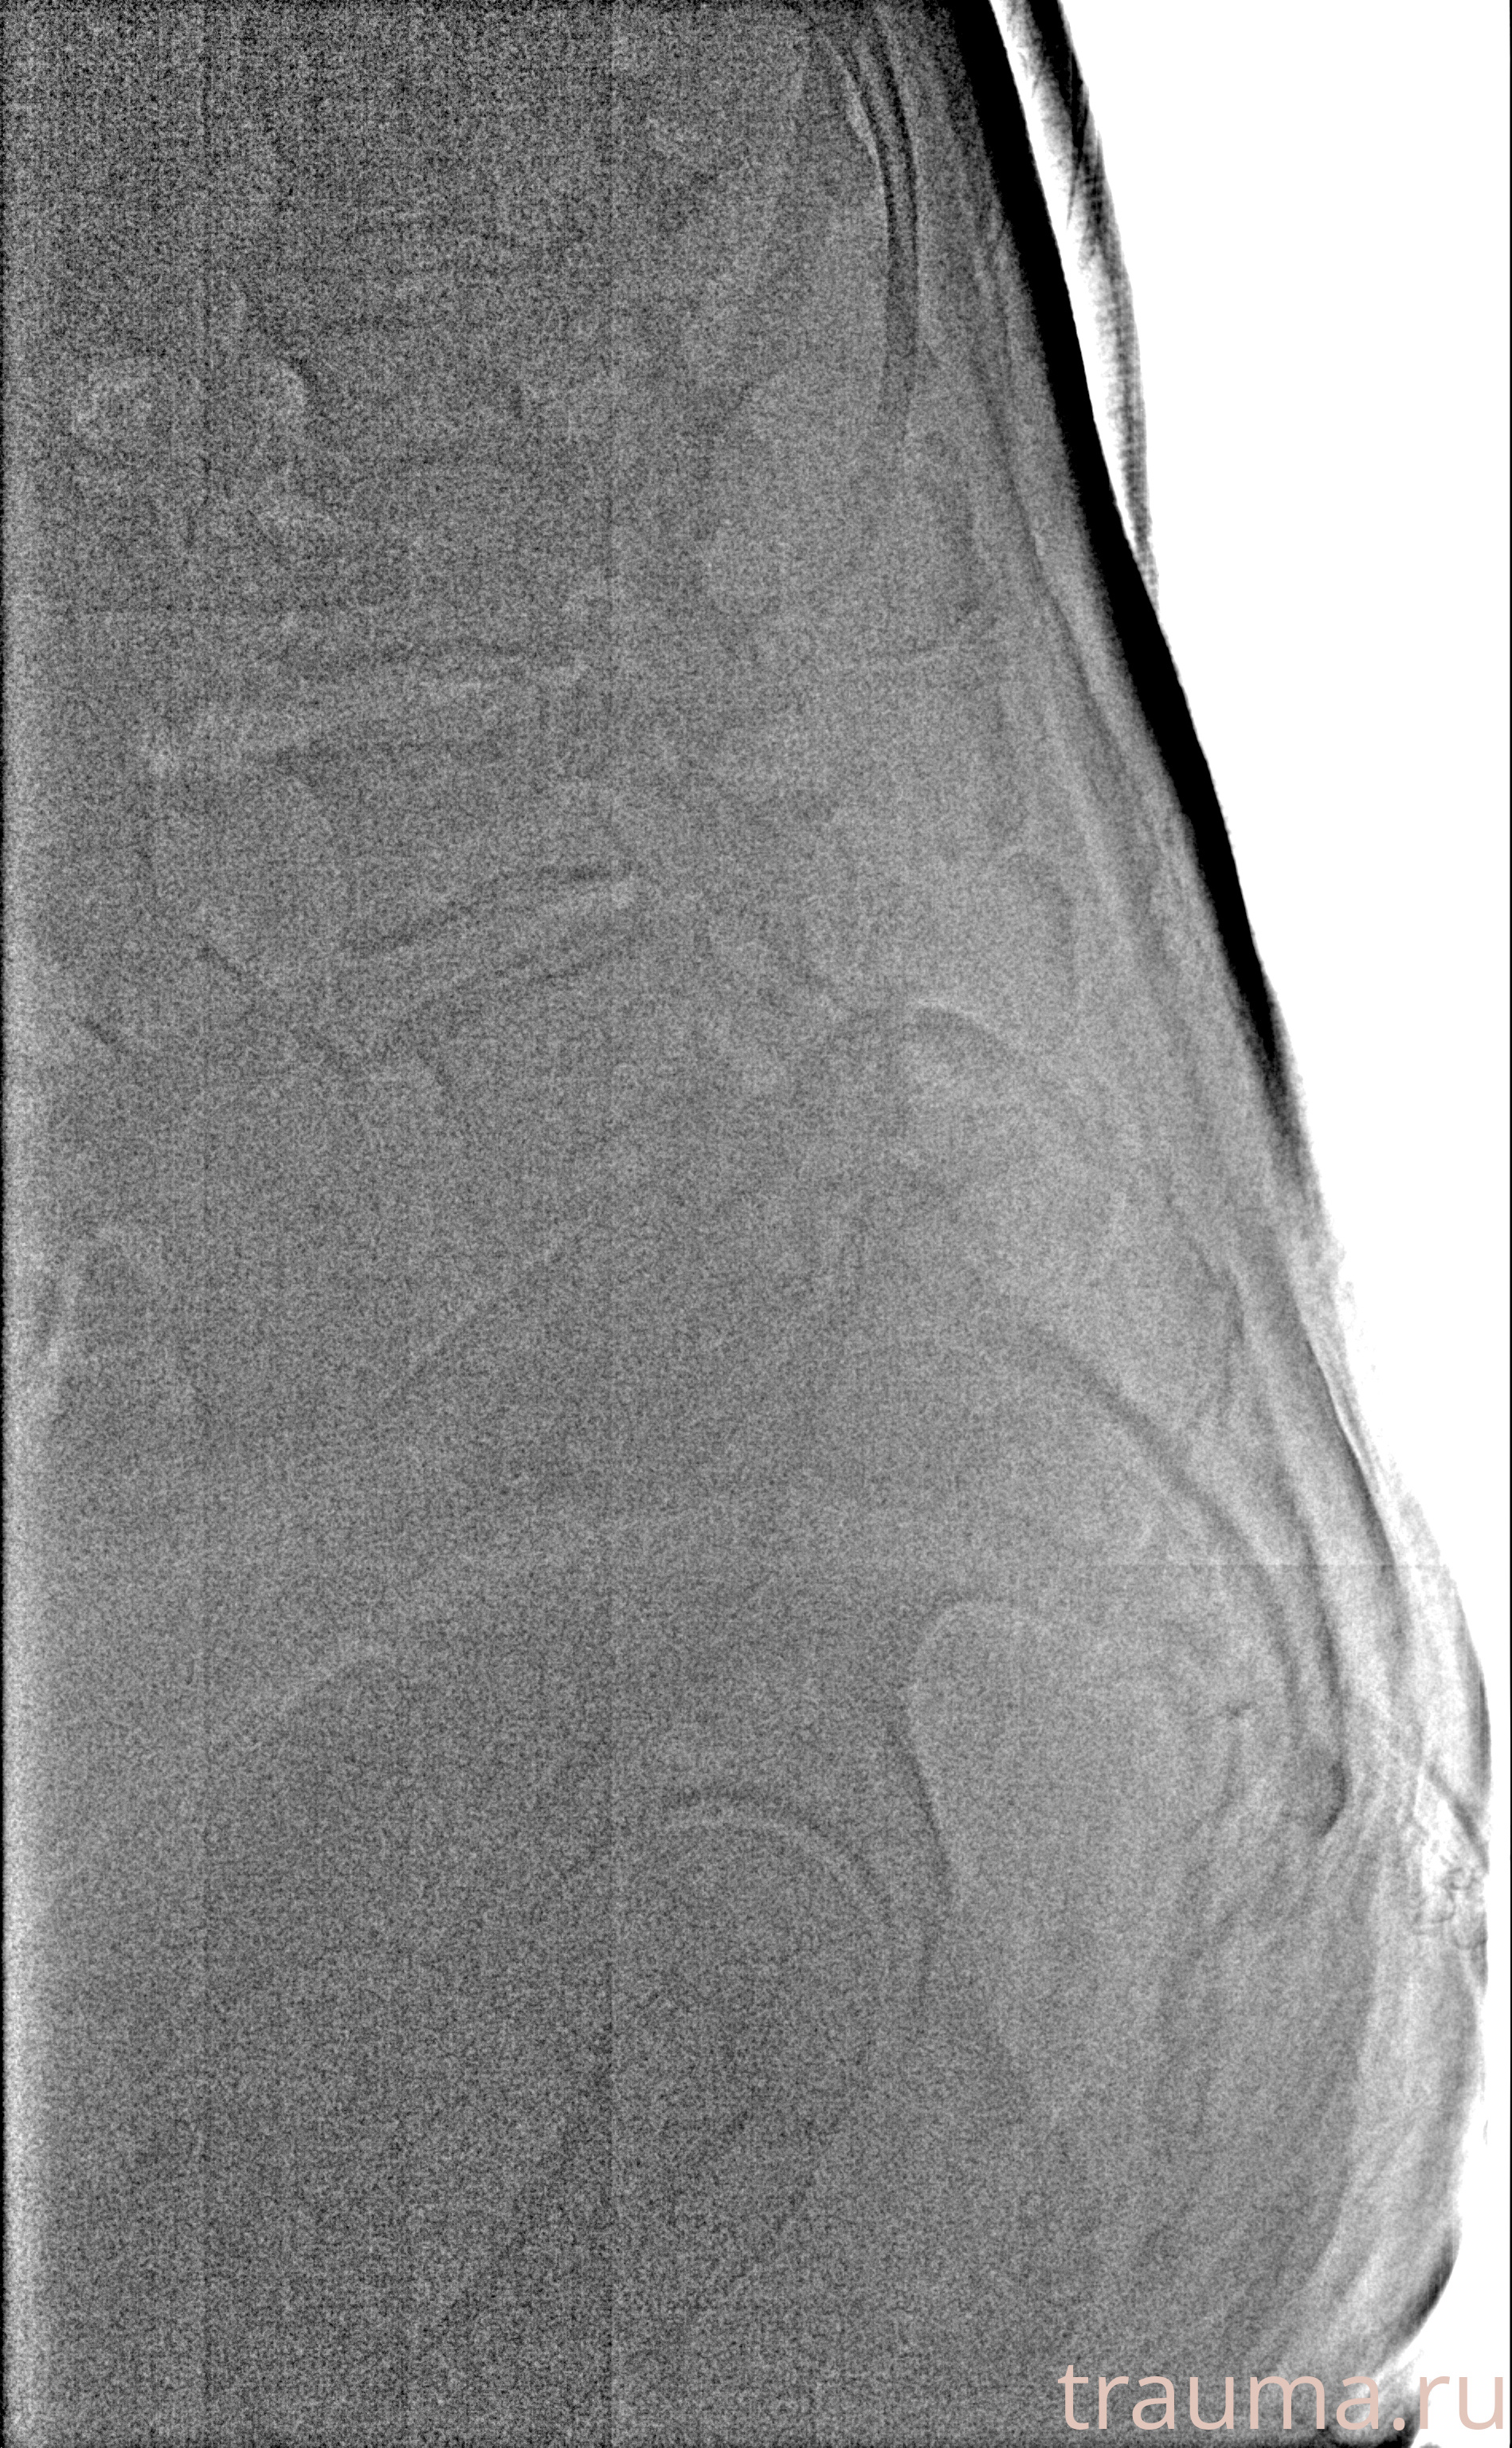

Рентген на дому: по вашему адресу приезжает врач-рентгенолог, травматолог-ортопед с мобильным рентгеновским аппаратом, проводит диагностику травмы или заболевания, делает необходимые рентгенограммы, дает рекомендации по дальнейшему лечению. Получить качественные снимки в домашних условиях возможно благодаря уникальной методике, разработанной МосРентген Центром для института  Склифосовского